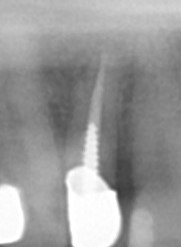

【水酸化カルシウム製剤を貼薬 のう胞まで薬剤が挿入されているのと側枝にも薬剤が入っている】

【歯根のう胞摘出後、術中根充 手術後半年】

【歯根のう胞腔は縮小し、骨が再生し不透過像になってきている】